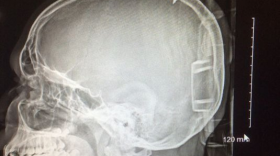

SALISBURY, Md. (AP) - A Maryland seventh-grader has survived after the tip of a 6-inch-long metal screw got lodged in his skull.The Daily Times of…